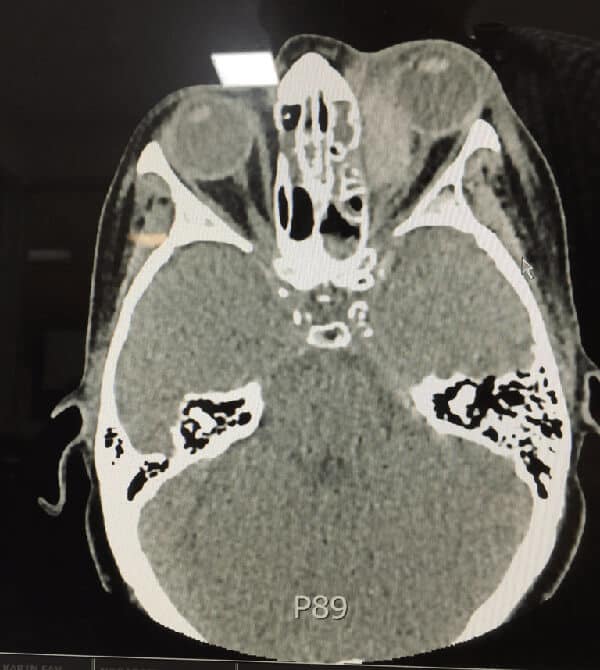

This is an ophthalmological emergency. In perfect world, the treatment should occur first, however because we did not know what was happening a rapid CT was done, which demonstrated a retrobulbar haematoma, causing the proptosis and a stretching of the optic nerve.